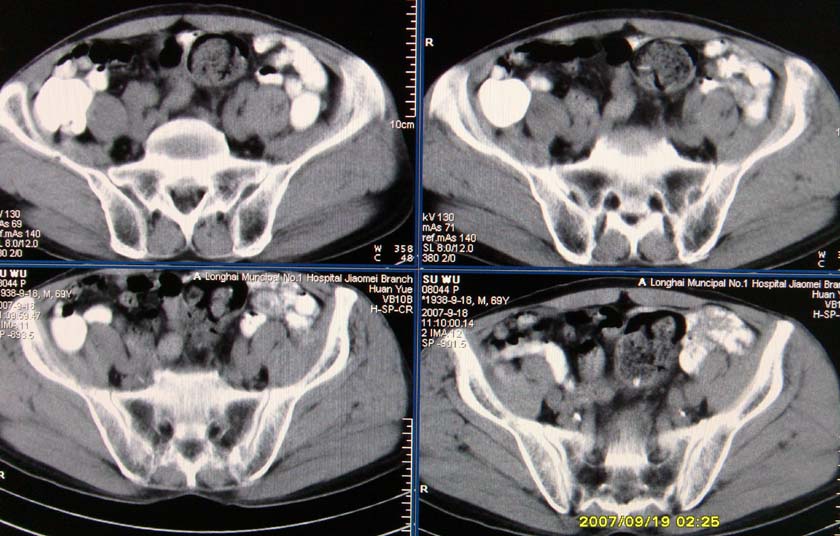

以下是引用xclzq_910在2007-9-19 16:58:00的发言:[br]直肠壁增厚,管腔偏移,直肠癌可能性大

以下是引用宝天曼在2007-9-19 21:11:00的发言:[br]根据直肠壁不规则增厚,考虑直肠肿瘤,不过最后的确诊还是需要肠镜.